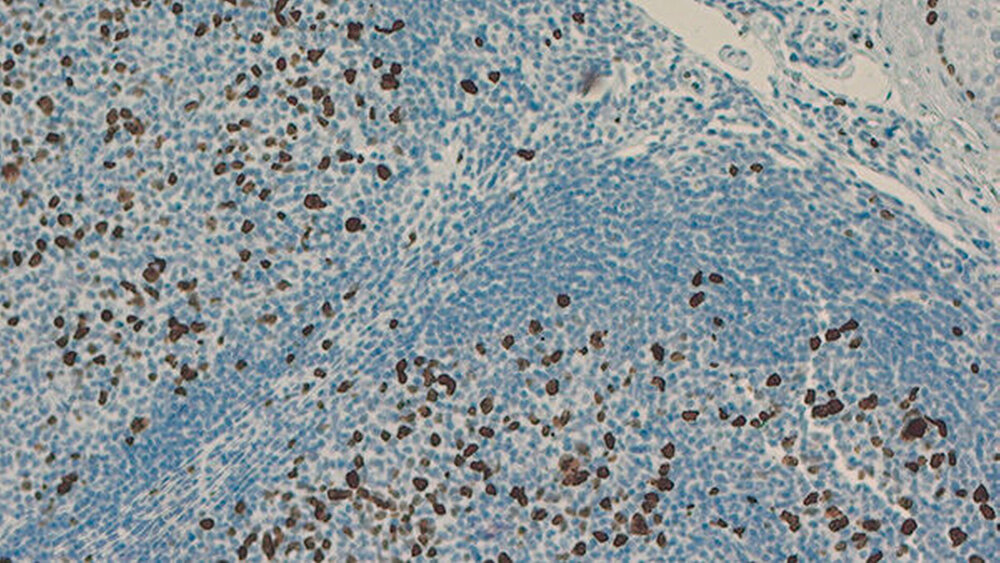

Das intraoperativ in toto resezierte Material (Abbildung 3) wurde zur genauen Dignitätsklärung histopathologisch aufgearbeitet. Bei der Begutachtung zeigte sich Speicheldrüsengewebe mit großen Bereichen atypischer, lymphoider Proliferation. Das Bild war bestimmt durch große Follikel beziehungsweise Pseudofollikel, teilweise ineinander übergehend, mit umgebenden interfollikulären Zonen. Die immunhistochemische Untersuchung ergab eine kräftige, vorwiegend follikuläre Anfärbung von CD20- und CD79a-positiven Zellen. Der Ki67-Proliferationsindex (Antigen Ki-67 ist ein Protein, das zur Markierung von sich teilenden menschlichen Zellen geeignet ist) ergab einen Anteil von 30 Prozent (Abbildung 4).